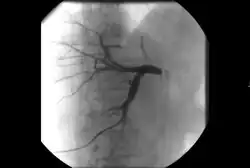

• Cholangiography: Imaging the bile ducts within the liver to look for areas of blockage.

Biliary stenosis

Biliary intervention[12]

• Placement of catheters in the biliary system to bypass biliary obstructions and decompress the biliary system.

• Placement of permanent indwelling biliary stents.

In addition to normal liver tissue, the liver has three main vessels traversing it: arteries, veins and bile ducts. While bile is made in the liver and stored in the gallbladder, the bile eventually passes into the GI tract through the hepatic, cystic and common bile ducts. Any condition that prevents the normal flow of bile from the liver, through these bile vessels and into the GI tract can cause a condition called jaundice.

While jaundice can be caused by a few viruses that the human body can naturally clear, jaundice in the setting of an obstruction is usually caused by a cancer and can result in intolerable itching and a worsening of liver function that can be life-threatening. Depending on a patient's condition, this type of obstructive jaundice can be alleviated with surgery or chemotherapy but if these measures fail to restore proper flow of bile, an interventional radiologist can perform a procedure called a percutaneous transhepatic cholangiography (PTC).[21]

A PTC is an outpatient procedure lasting anywhere from 15 minutes to an hour where an interventional radiologist accesses the patient's bile duct system with a needle through the skin and liver under imaging guidance. Using fluoroscopy (essentially an X-ray camera) to guide a wire (followed by a catheter over the wire) through the bile duct system and into the GI tract, essentially restoring the normal flow of bile. If the patient's GI tract cannot be accessed due to the obstruction, the catheter can be placed to drain the bile duct system into a bag that the patient can wear during daily activities. Risks of this procedure include bleeding and infection but these are much lower than an equivalent surgical procedure.[21]